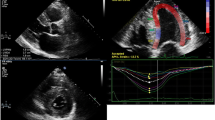

Echocardiography is the most accessible and first line imaging tool in the approach towards assessing patients with cardiomyopathy. The amyloid phenotype is one of characteristic biventricular wall thickening with small, non-dilated ventricles and left ventricular (LV) wall thickness typically greater than 12 mm (Fig. 1). There is a tendency towards a symmetrical increase in LV wall thickness in AL CA, while ATTR CA more often demonstrates an asymmetrical pattern. [22, 23•] In the latter, the morphology of the septum may be sigmoid (seen in 70%) or demonstrate inversion of the septal curvature (seen in 30%). [22] Although patients with ATTR CA typically have higher LV and RV mass at diagnosis, which may in fact reflect earlier clinical presentation in patients with AL CA [24], LV mass in isolation is unsuited to differentiate between the types. Well described but non-specific findings of CA include a thickened and sparkling appearance of the valves and interatrial septum, as well as a ‘speckled’ appearance of the myocardium. Pericardial and pleural effusions are also relatively common findings, especially in AL amyloidosis.

Top Panel: Echocardiography findings in a patient with advanced cardiac amyloidosis. (a) Parasternal long axis view and (b) four chamber view showing concentric left ventricular hypertrophy (c) pulse wave Doppler showing restrictive left ventricular inflow pattern (d) strain pattern characteristic of an infiltrative process. Bottom Panel: CMR findings in a patient with advanced cardiac amyloidosis. (e) Four chamber steady state free precession cine demonstrating left ventricular hypertrophy (f) corresponding native T1 map showing a T1 value of 1150 ms in the basal inferoseptum (g) corresponding T2 map showing a T2 value of 54 ms in the basal inferoseptum, within normal limits (h) corresponding phase sensitive inversion recovery reconstruction showing transmural late gadolinium enhancement (i) corresponding extracellular volume map showing elevated value of 0.70

Amyloid infiltration in the extracellular space leads to ventricular stiffening, impaired relaxation and biventricular diastolic dysfunction, which in combination with direct atrial amyloid infiltration can lead to atrial dilatation, blood stasis and a higher risk of thrombus formation [25,26,27,28]. Although CA is traditionally categorized as a cause of ‘heart failure with preserved EF’, this under-represents the extent of involvement of both systolic and diastolic dysfunction. Ejection fraction, which is a widely relied upon measure of ventricular function is not a reliable indicator of systolic function in CA as EF reflects radial contraction which is often preserved until end stage disease. Longitudinal function is typically affected earlier than radial contraction and indices of longitudinal function can be used as early disease markers. This was initially demonstrated measuring the systolic excursion of the mitral annulus evaluated by Tissue Doppler imaging (TDI) or from M-mode derived mitral annular plane systolic excursion (MAPSE) [29, 30], and later on with strain imaging. Longitudinal strain (LS) measurement by tissue Doppler and echocardiographic speckle tracking are proving to be valued tools in diagnosing CA, as well as differentiating CA from other hypertrophic phenocopies [3]. Strain demonstrates not only reduction in longitudinal contraction, but also reduction in LS that affects predominantly the basal segments with sparing of the apical segments. This is a highly characteristic feature of CA, which gives rise to the typical appearance of a ‘bull’s eye pattern’ with strain values that are reduced on the side and preserved in the centre of the plot (Fig. 1) [3, 31]. The extent of apical sparing can be quantified using relative ratio between apical and basal LV regional strain, which is also associated with poorer prognosis [32].

In CA patients diastolic function is almost invariably impaired and the degree of impairment ranges from impaired relaxation to restrictive filling patterns [33]. Parameters of diastolic dysfunction can also be used as early disease markers, with TDI of the mitral annulus often being less than 6 cm/s (Fig. 1) [34].